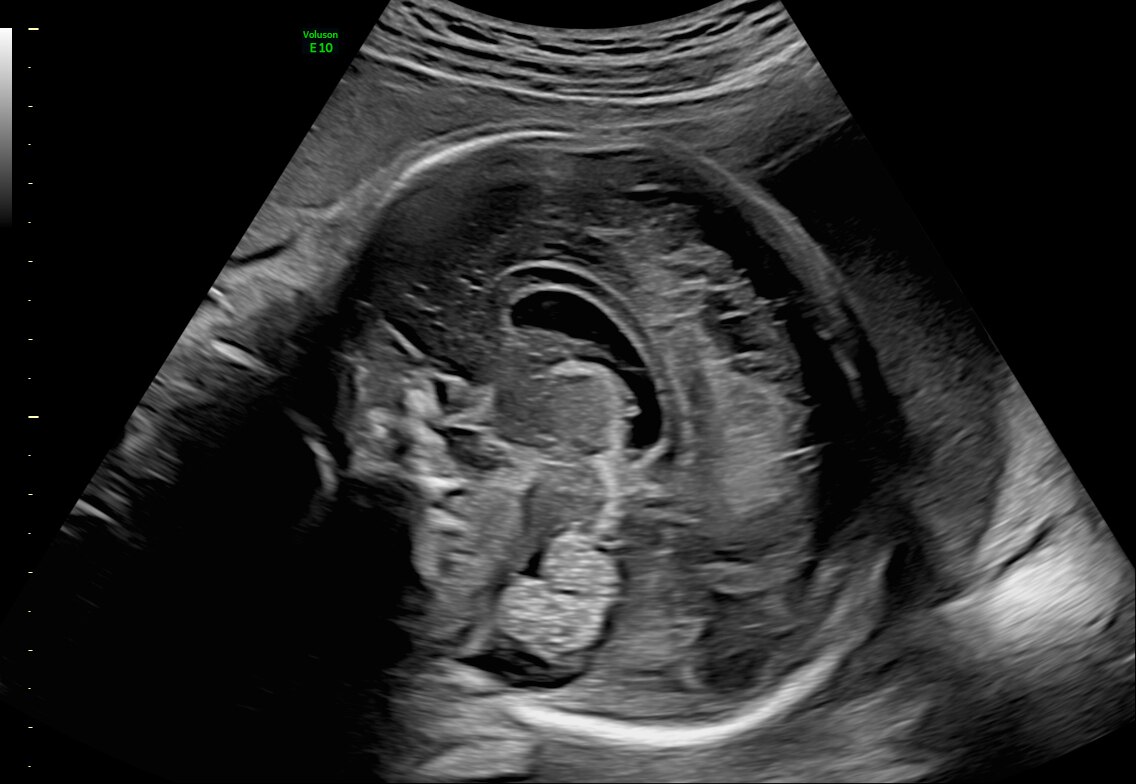

Fetal brain with C2-9 probe and HDRes